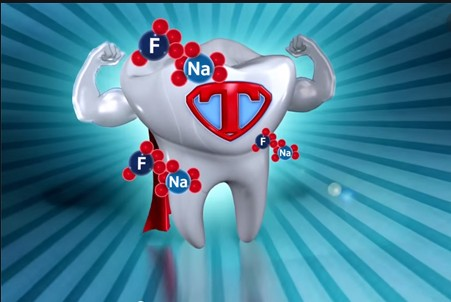

- When your dentist detects a weak spot on your tooth, at-home flouride treatments may be recommended to reverse

When your dentist detects a weak spot on your tooth, at-home flouride treatments may be recommended to reverse

thedecay process. if the weak spot is left unchecked, a cavity may form, necessitating a filling. If decay is allowed to

to spread, it may penetrate the root and enter the pulp (nerve) chamber, causing an abscess and requiring root canal treatment

PROGRESSION OF TOOTH DECAY

Tooth decay often beginson biting surfaces, between the teeth, and on exposed roots.

Untreated, the cavity becomes larger.

Decay spreads beneath the enamel and can destroy the tooth structure.

Decay enters the pulp and an abscess may occur

Use of flouridated toothpaste can help prevent tooth decay at its early stage.

Tooth enamel is hard and porous. it consists of many closely-packed rods made of minerals.When you

eat, acid forms on theoutside of the tooth and seeps into the enamel's pores.This deminerilization process can produce a weak spot

in the tooth's surface. if unchecked, the enamel can decay and create a cavity.

Fluoride helps prevent tooth decay by slowing the breakdown of enamel and speeding up the natural remineralization

process. These microscopic views of the tooth's chewing surface show how flouride works.

Healthy tooth enamel rods before acid's onslaught.

Enamel rods demineralized, or broken down, by acid.

Enamel rods remineralized, or rebuilt, by fluoride and the minerals in saliva.

Common sources of flouride are fluoridated drinking water, toothpaste and mouth rinse. inform your dentist if your

drinking water is not fluoridated. High concentration fluoride gels, mouth rinses, drops and tablets are available by prescription.